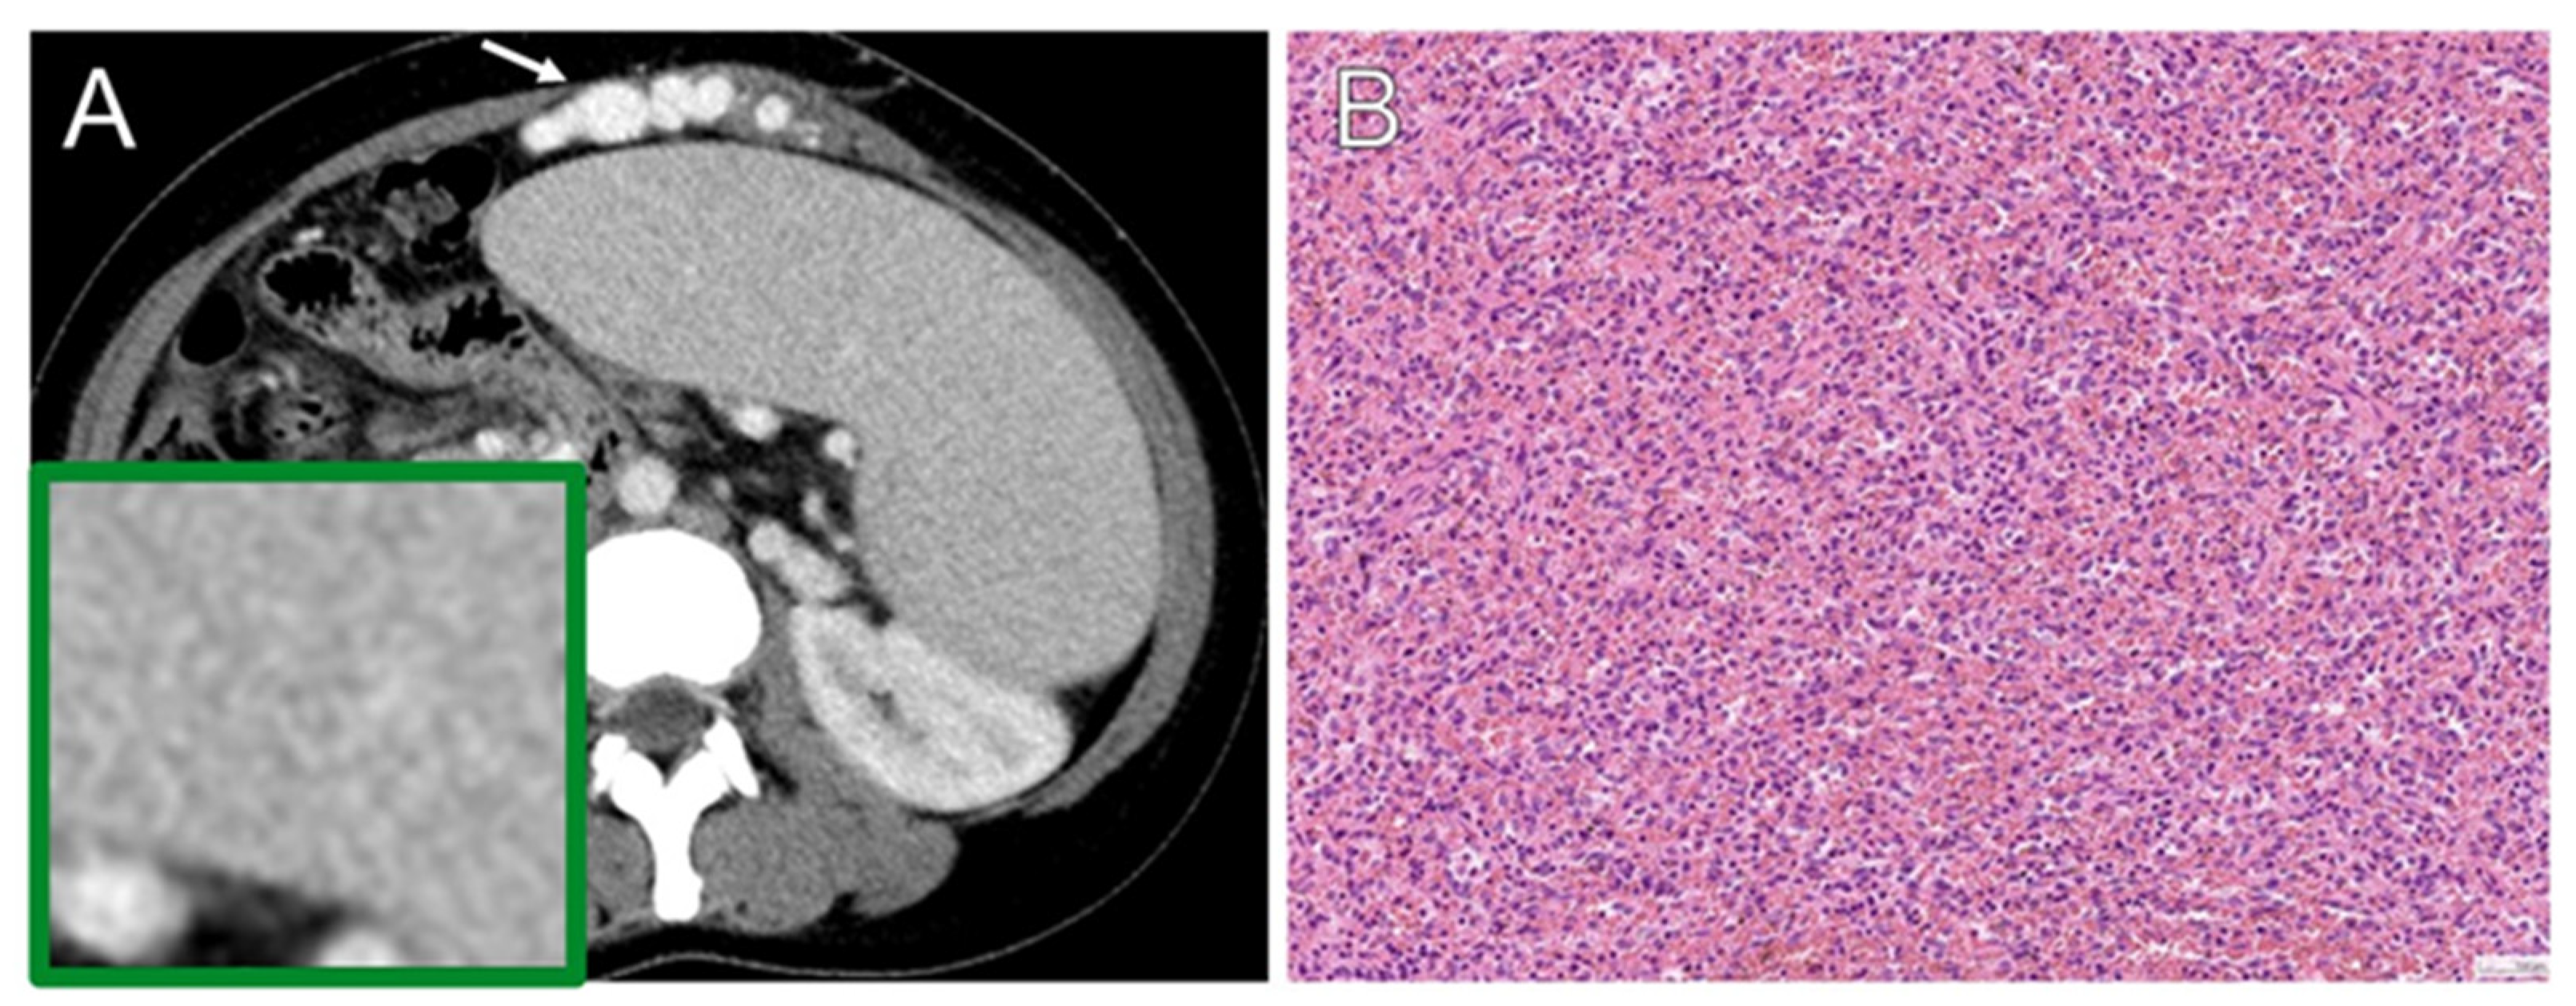

2. Related Work

3.1. Study Patients

3.4. Splenectomy Cause

3.5. Histopathology